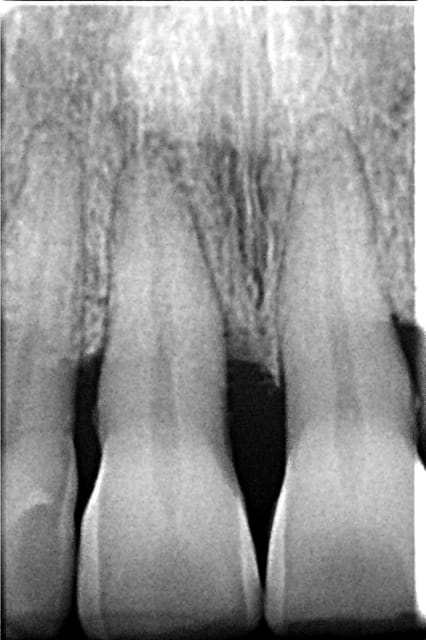

Patiente ayant traversé sa véranda en mars: choc sur la 11.

Revue par une consoeur pendant ma longue absence (perte de la contention que je lui avais placé)

Je la revois auj:

légère mobilité

Mais radiologiquement, je suis dubitatif:

Votre avis?

Positif, mais la lamina dura en mésial m'inquiète

Il peut s'agir d'un début de résorption externe. A suivre de près.

Le test de vitalité est toujours positif et surtout avec une réponse identique sur 11 et 21.

Radiologiquement, pas d'évolution notable. Une incidence un peu plus mésiale me laissse entrevoir une lamina dura bien délimitée sur un bon 1/3 cervical du desmodonte mésial.